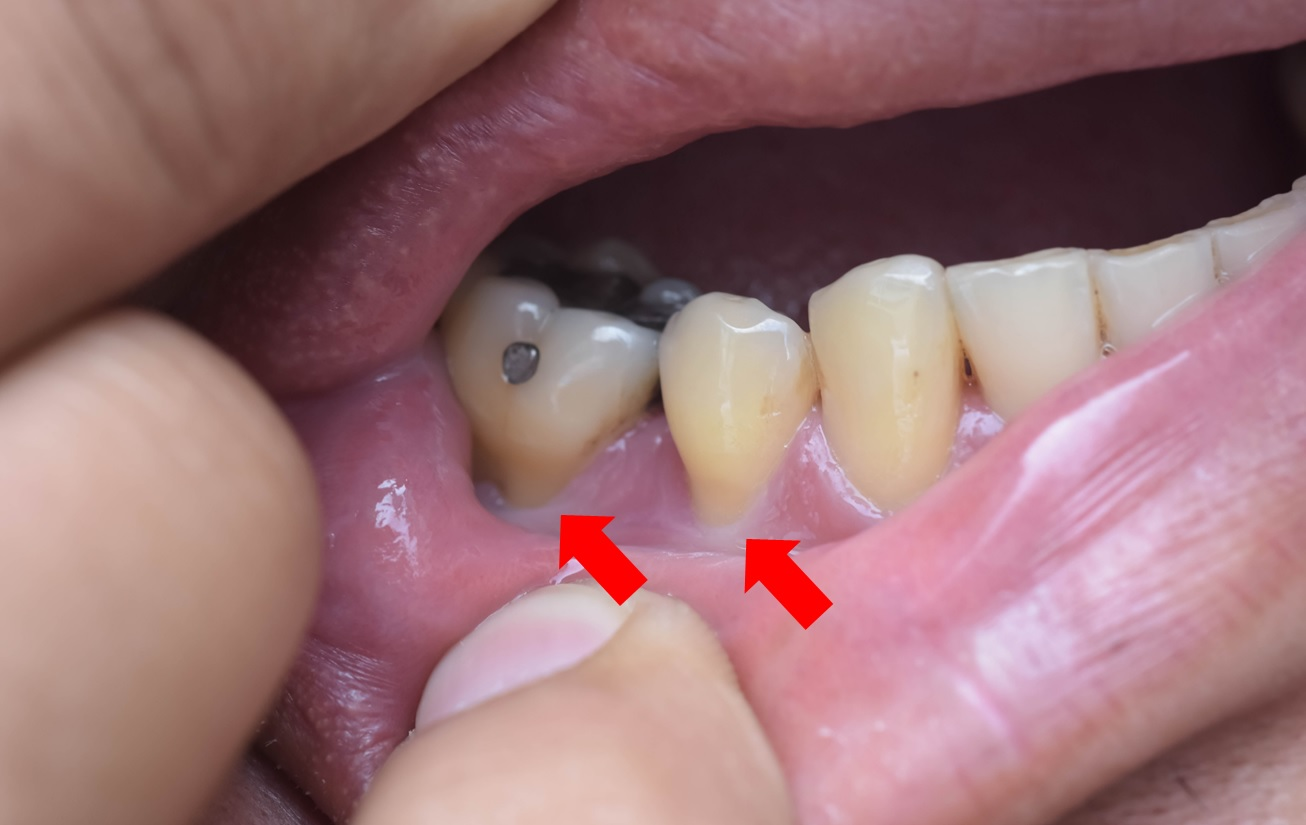

2. 歯茎部アブフラクション(cervical abfraction)

歯の噛む(biting)力、また歯ぎしりをする(grinding)力によって歯の首(cervical)部位にエナメルの微小破壊(micro-fracture)が発生します。

エナメルは薄いガラスを何枚かを重ねたような構造になっていて、絵で見られるようにとられる傾向があります。

こういう現象をアブフラクション(abfraction)といいます。この際に象牙質が現れ、歯の中にある神経がしびれ感を感じられるようになります。

位置上、主に歯の頬っぺた側(buccal・バッカル)、唇側(labial)のエナメルとセメント質の境目にある歯の首(cervical)部位から発生します。掘られた形が深い楔(wedge)の形です。